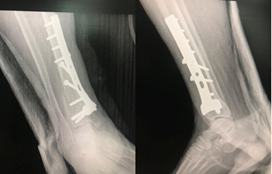

A 58-year-old woman presented in July 2017 to the Emergency Department at Hassan II University Hospital, Morocco, due to the rapid onset of fever, and a suspected skin infection. She had a previous medical history of a fracture of the lower quarter of the leg which was treated by a plate osteosynthesis (Figure 1) (Figure 2). She had a sharply demarcated, warm, and painful erythema on her leg surmounted by vesicles in places, purpuric by others, taking the operative scar (Figure 3). Vital parameters showed a temperature of 38.0°C, respiratory rate of 18breaths/min, O2 saturation of 96% on room air, heart rate of 80beats/min, and blood pressure of 120/70mmHg. Oral examination showed no signs of infection, and examination of lymph nodes was normal. Her laboratory results showed a white blood cell count of 22100/mm3, her CRP was 235mg/L. The radiological examination of the leg revealed a fracture in the process of consolidation without radiological signs of sepsis on the osteosynthesis material. She was clinically diagnosed with erysipelas she was treated with intravenous amoxicillin + clavulanic acid. Clinical and biological improvement was noted, resulting in the switch to the oral route on the fifth day of treatment. The patient received 21days of antibiotic therapy. The evolution was marked by the complete disappearance of the cupboard with a decline of 1 year and a half without recurrence.

Figure 1 Radiography of the ankle showing a fracture of the lower quarter of the leg.

Figure 2 Control radiography after 3 months of postoperative surgery not showing signs of sepsis on material, with beginning of consolidation.